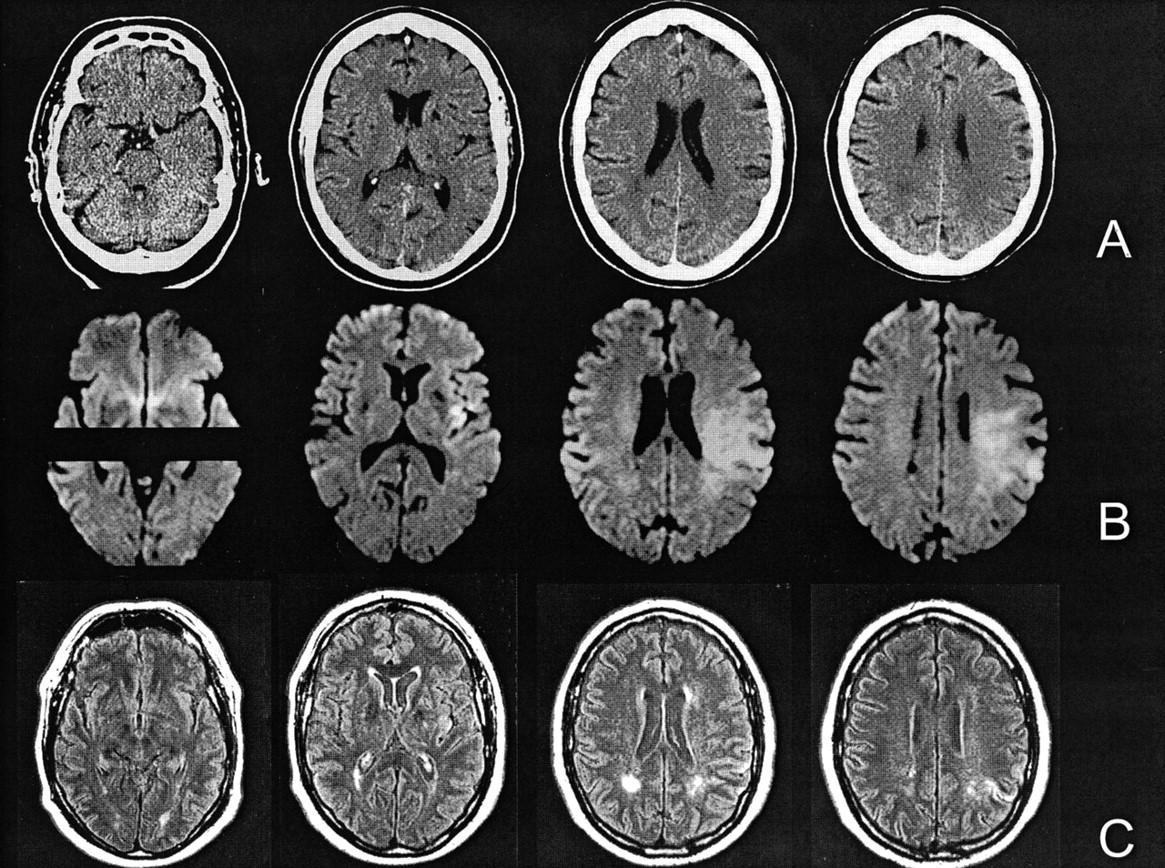

Computerized Axial Tomography (CAT/CT Scan) → a sophisticated xray

Xray cameras that rotate around the brain

3D picture of the brain’s structure, no function or activity

Exposed to carcinogenic radiation

Magnetic Resonance Imaging (MRI) → uses magnetic fields/radio waves to measure density and location of brain material

More detailed